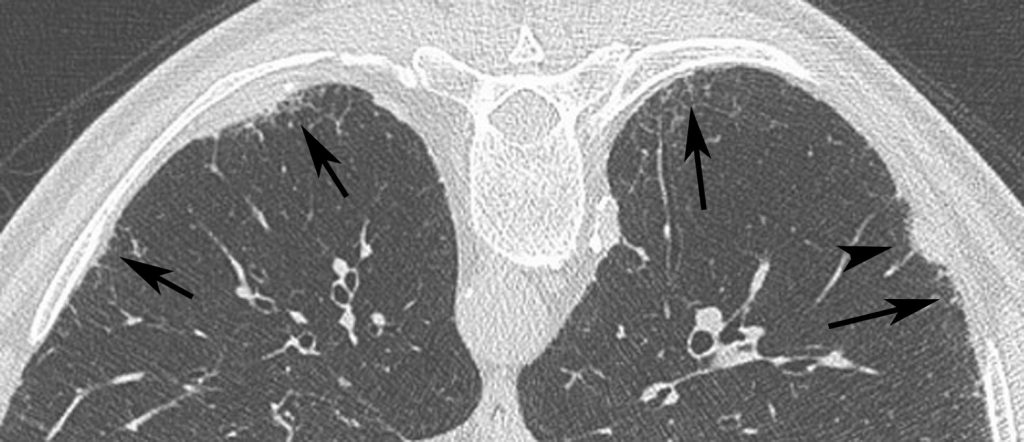

Fig. 95.3. Asbestose.

Image de scanner sans injection en décubitus ventral, en coupe axiale, évocatrice avec des réticulations et des micronodules centrolobulaires (flèches) associés à une plaque pleurale (tête de flèche) et situés dans les culs-de-sac postérieurs et le cortex du poumon.

Source : CERF, CNEBMN, 2022.